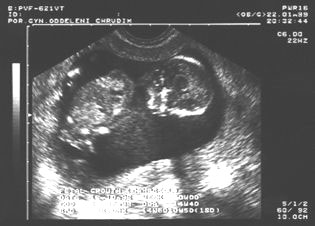

10. týden: dvojvaječná dvojčata

10.týden